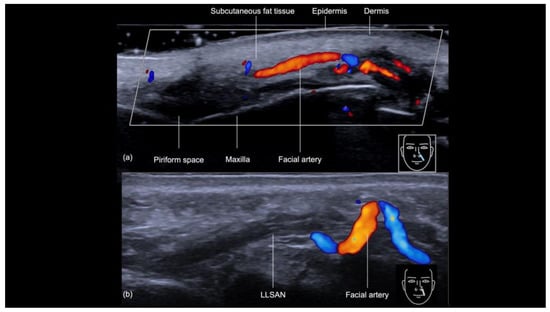

3.3. Nasolabial Fold

3.3.1. Sonographic Anatomy of the Nasolabial Fold

3.3.2. Ultrasound-Guided Filling Techniques of the Nasolabial Region

- Technique 1: Subcutaneous filler placement with a blunt cannula

- Technique 2: Supraperiosteal filler placement with a needle